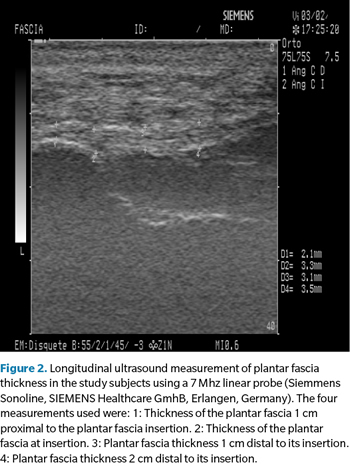

Outcomes

Clinical outcomes were measured using a 20 centimeter-long visual analogue scale (VAS) with 6 graduated images (faces) on one side indicating pain sensations ranging from no pain to extreme pain. On the other side, the scale presented a numerical graduation that corresponded to the different sides shown. This scale is validated and universally accepted as an instrument for measuring pain intensity18,19. Patients assessed the degree of pain in the first steps of the morning in the area of the scale where the images were displayed and the examiner wrote down the numerical value to which the area of the scale selected by the patient corresponded. The thickness of the plantar fascia was also measured sonographycally at 4 different locations in all patients. The ultrasound assessment was performed using an ultrasound with a 7 Mhz linear probe (Siemmens Sonoline, SIEMENS Healthcare GmhB, Erlangen, Germany) with the patient in the supine position where a sagittal section image was taken of the plantar fascia corresponding to the area of greatest thickening in each patient. On this image, measurements of plantar fascia thickness were taken at 4 different locations: plantar fascia thickness 1 cm proximal to insertion, plantar fascia thickness at insertion, plantar fascia thickness 1 cm distal to insertion and plantar fascia thickness 2 cm distal to insertion as described by Pascual et al.20 (Figure 2). Both measurements (VAS and ultrasound) were taken on the first day of the patient’s consultation, which was considered the PRE value, and were repeated at one month, three months and six months of treatment. Likewise, all measurements were taken by the same observer who performed the biomechanical examinations and the prescription of the insoles.